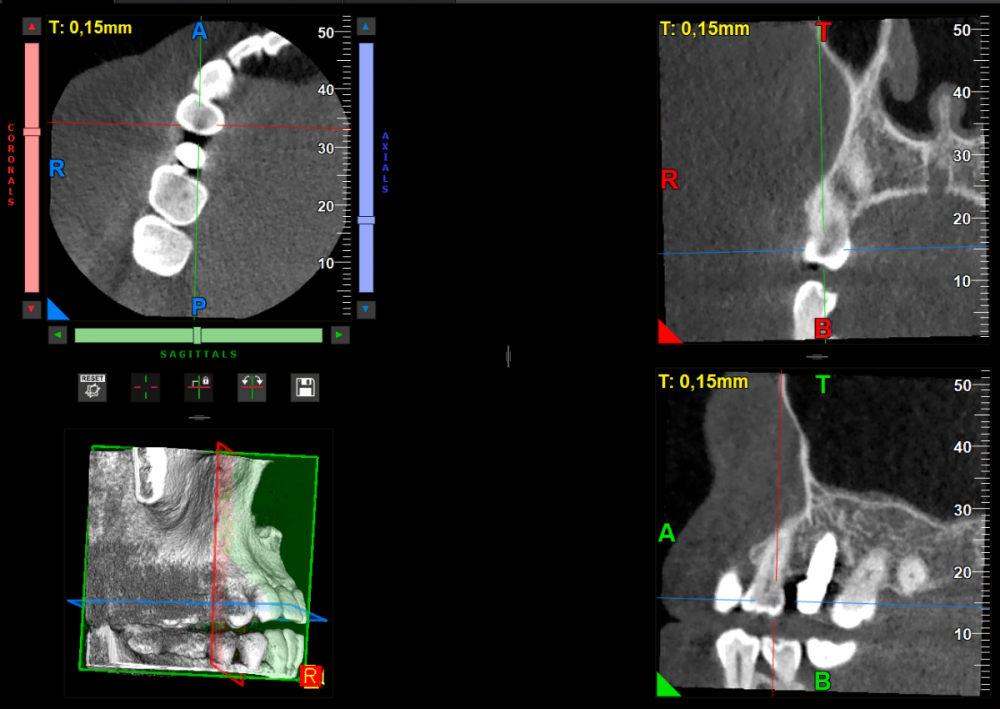

Dashik Опубликовано 14 февраля, 2024 Автор Поделиться Опубликовано 14 февраля, 2024 Добрый вечер! Сделала я КТ проблемной зоны. Смотрю и думаю: какие скриншоты выложить для подтверждения диагноза... Даже не знаю. Полная ссылка на кт с файлами и просмотрщиком ниже https://drive.google.com/drive/folders/10yxukA7lUYpJQL0ARJDSEpluF9Wc3mLa?usp=sharing Всем, кто может посмотреть, огромное спасибо! Ссылка на комментарий

Carioznik Опубликовано 16 февраля, 2024 Поделиться Опубликовано 16 февраля, 2024 вижу по КТ кариес и немаленький! 1 Ссылка на комментарий

Carioznik Опубликовано 17 февраля, 2024 Поделиться Опубликовано 17 февраля, 2024 (изменено) 16.02.2024 в 15:06, Dashik сказал: А на 16 зубе под пломбой? Похоже на кариес, но не точно. И на нижнем зубе (46) тоже. Но может это артефакты. 21 час назад, Dashik сказал: КТ виден на корне 14 зуба камен Такое сложно увидеть, тем более, КТ по качеству не очень(либо у меня не получается настроить нормальную визуализацию в этом просмотрщике) Ps : Чтобы не было ошибок в диагностике, кроме КТ нужен ещё очный осмотр. И уже на основе как осмотра так и КТ - уже ставится диагноз Изменено 17 февраля, 2024 пользователем Carioznik 1 Ссылка на комментарий

Dashik Опубликовано 20 февраля, 2024 Автор Поделиться Опубликовано 20 февраля, 2024 (изменено) Огромное спасибо за потраченное время! Я была очно на приёме у доктора в Москве, там же мне делали и КТ. Насчёт качества аппарата не спрашивала, подумала, что у хорошего врача и аппарат будет хороший. Врача я выбирала по ссылке у Петра Лазукина в публичной группе "Обучение". Первоначально я хотела в другую клинику, где с качеством КТ точно не было бы проблем. Но мне в консультации отказали, аргументировав, что временная коронка не долговечна и её всё равно надо менять, а мы чужие работы не исправляем! Но да ладно. Врач очень доброжелательный, посмотрел все зубы, просмотрел 14 и 16 зубы внимательно на КТ, в профессионализме сомнений нет . Увидел камень на 14 зубе на снимке, убрал. Честно говоря, я подумала, что если увидел камень, то и кариес тоже увидит. Никакого кариеса он не увидел. Сказал, при случае сделать реставрацию 16 зуба как-нибудь. Посмотрел прикус. Потом позвал даже своего ортопеда, чтобы он тоже посмотрел контакты. Ортопед увидел на 3 нижней слева мизерный суперконтакт, сказал можно и резинкой убрать и то что коронка без нагрузки, но это мне уже и в Дмитрове в зеркале показывали. Ничего я не понимаю: есть темное пятно на фото, сделанное ассистентом врача, на кт даже я вижу не специалист в данной области вижу затемнение, но при этом на очной консультации кариес не обнаружен. Мне ещё на одну консультацию записываться? Изменено 20 февраля, 2024 пользователем Dashik Ссылка на комментарий

Carioznik Опубликовано 21 февраля, 2024 Поделиться Опубликовано 21 февраля, 2024 (изменено) Насчёт качества КТ -это мое личное мнение. Просмотрщик КТ для меня не знакомый , и возможно в нем достаточно просто настроить визуализацию получше, но в этом нужно разбираться... Я посмотрел, так сказать, по быстрому, и на тех настройках в которых разобрался, и по моему мнению - там есть кариес. Но я не исключаю, что это может быть и артефакт, который можно принять за кариес. (Поэтому и спрашивал про обычный снимок, на котором я кариес не вижу). Поэтому, ставить у Вас диагноз только лишь по КТ - не верно. Можете сходить ещё на один осмотр, если сильно переживайте по этому поводу. Изменено 21 февраля, 2024 пользователем Carioznik 1 Ссылка на комментарий